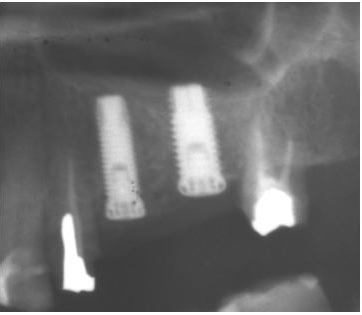

1.ソケットリフト症例(症例 7)

第1大臼歯部が7mmの骨しかないので、ソケットリフトにて4mmの上顎洞底挙上を行った。

ソケットリフトはほとんど腫れることはありませんが、骨が6mm未満では適応しにくく、骨を確実に増やすにはサイナスリフトの方が適しています。